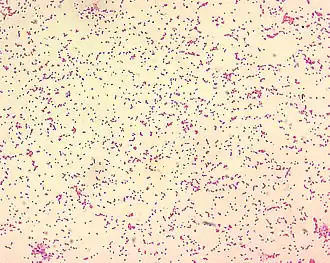

Vista ao microscópio.

Brucella é uma bactéria gram-negativa que pertence à família Brucellaceae. As células possuem forma de bastonetes curtos e ovais (bacilos/cocobacilos) imóveis, normalmente isoladas ou, com menor aparição, aos pares ou em cadeias curtas.